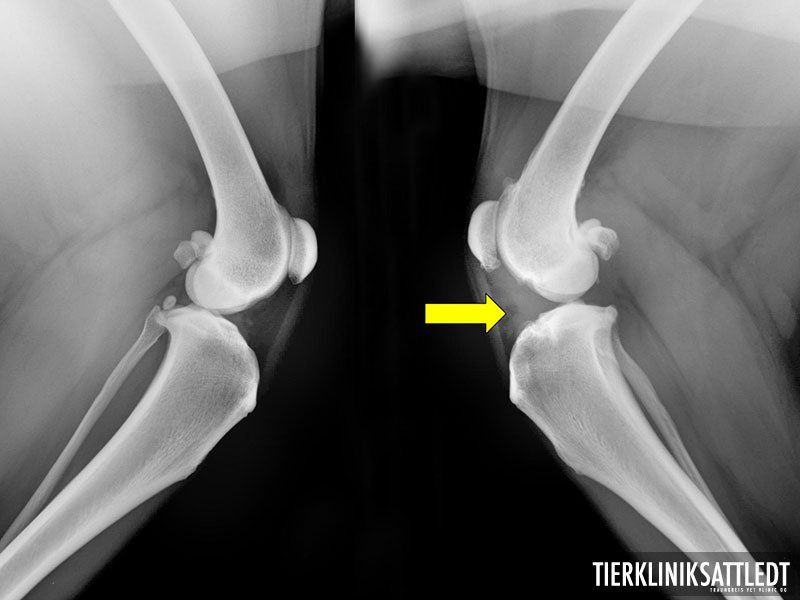

Das Knieglenk ist ein zusammengesetztes Gelenk und besteht eigentlich aus zwei Gelenken: dem Kniescheibengelenk und dem Kniekehlgelenk.

Stabilisiert wird es durch Seitenbänder, zwei Menisken, umliegende Muskulatur, sowie durch das vordere und hintere Kreuzband. Die Kreuzbänder führen das Gelenk in der Bewegung und begrenzen die Streckung und Rotation des Schienbeins.

Die Folge des Kreuzbandrisses ist eine Gelenkentzündung, sowie eine Instabilität. Diese Entzündnung führt dann wiederum durch die degenerative Veränderung zu einer Arthrose. Durch die Gelenkinstabilität werden weitere Strukturen überbelastet. Die Gelenkkapsel versucht durch Verdickung das Kniegelenk zu stabilisieren. Häufig wird der innere Meniskus überstrapaziert, welcher dann ebenfalls reißen kann.